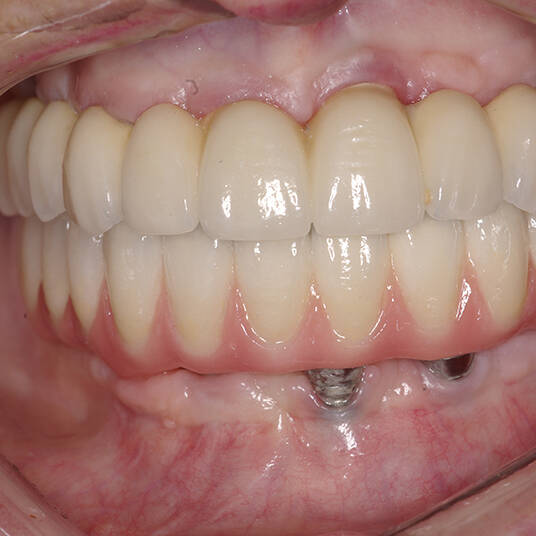

- Fixação da Prótese: Em até 72 horas após a cirurgia, a prótese provisória é instalada, permitindo que o paciente recupere a funcionalidade e a estética imediatamente.

- Conforto e Estética: A prótese provisória é funcional e visualmente semelhante aos dentes naturais.